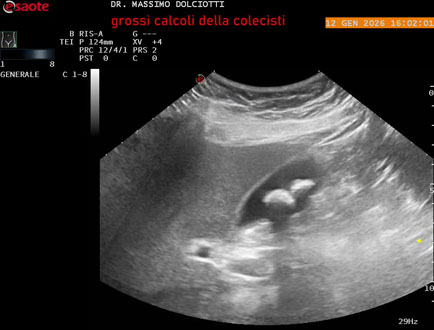

Data inserimento: 23/12/2024

Ecografia del: 16/12/2024

Strumento: Esaote MyLab Eight

Sonda: Convex Multifrequenza 1-8 MHz

Età Paziente: M 55 anni

Motivazione dell'esame: follow up per litiasi della colecisti.

Commento all'esame: le immagini ed il video documentano nel lume della colecisti, due immagini iperecogene, con cono d'ombra posteriore, delle dimensioni di 19,5 mm e 18,4 mm, da ricondurre a litiasi multipla.

Conclusioni: due grossi calcoli della colecisti (two large gallstones).

Presentazione: Dr. Massimo Dolciotti - Ancona

Elaborazione digitale: Andrea Dini - Ancona